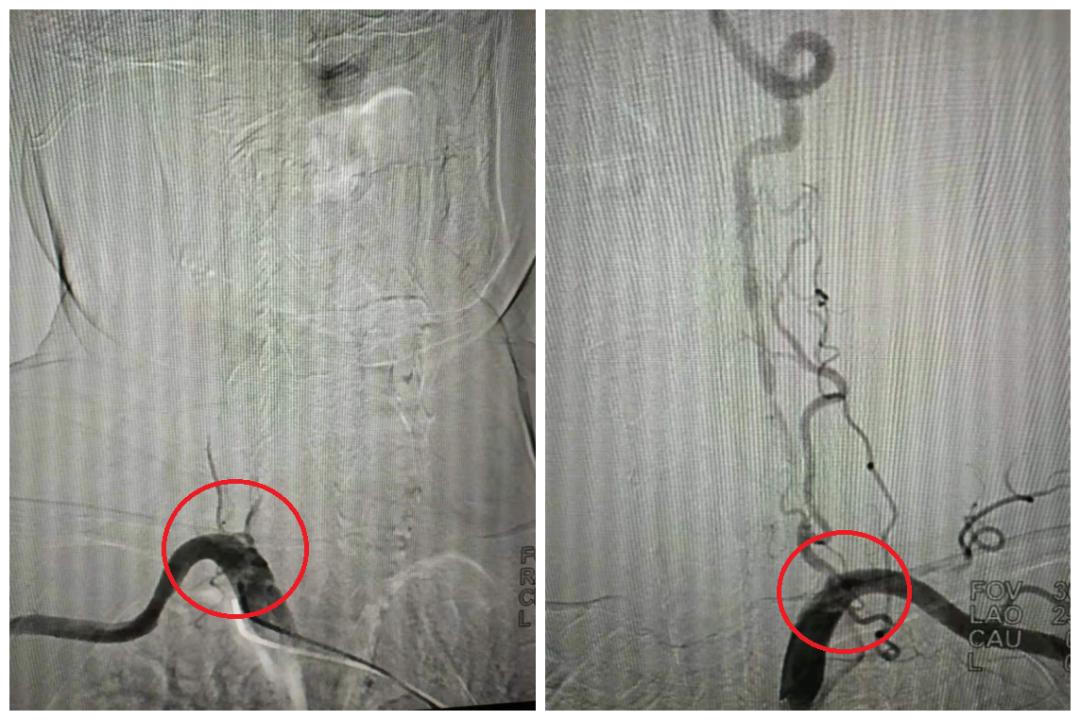

双侧椎动脉起始段闭塞(局部),右图含侧支代偿

双侧颈动脉C1段狭窄(局部)

右颈C1支架置入术前(左)术后(右)

左颈C1支架置入术前(左)术后(右)